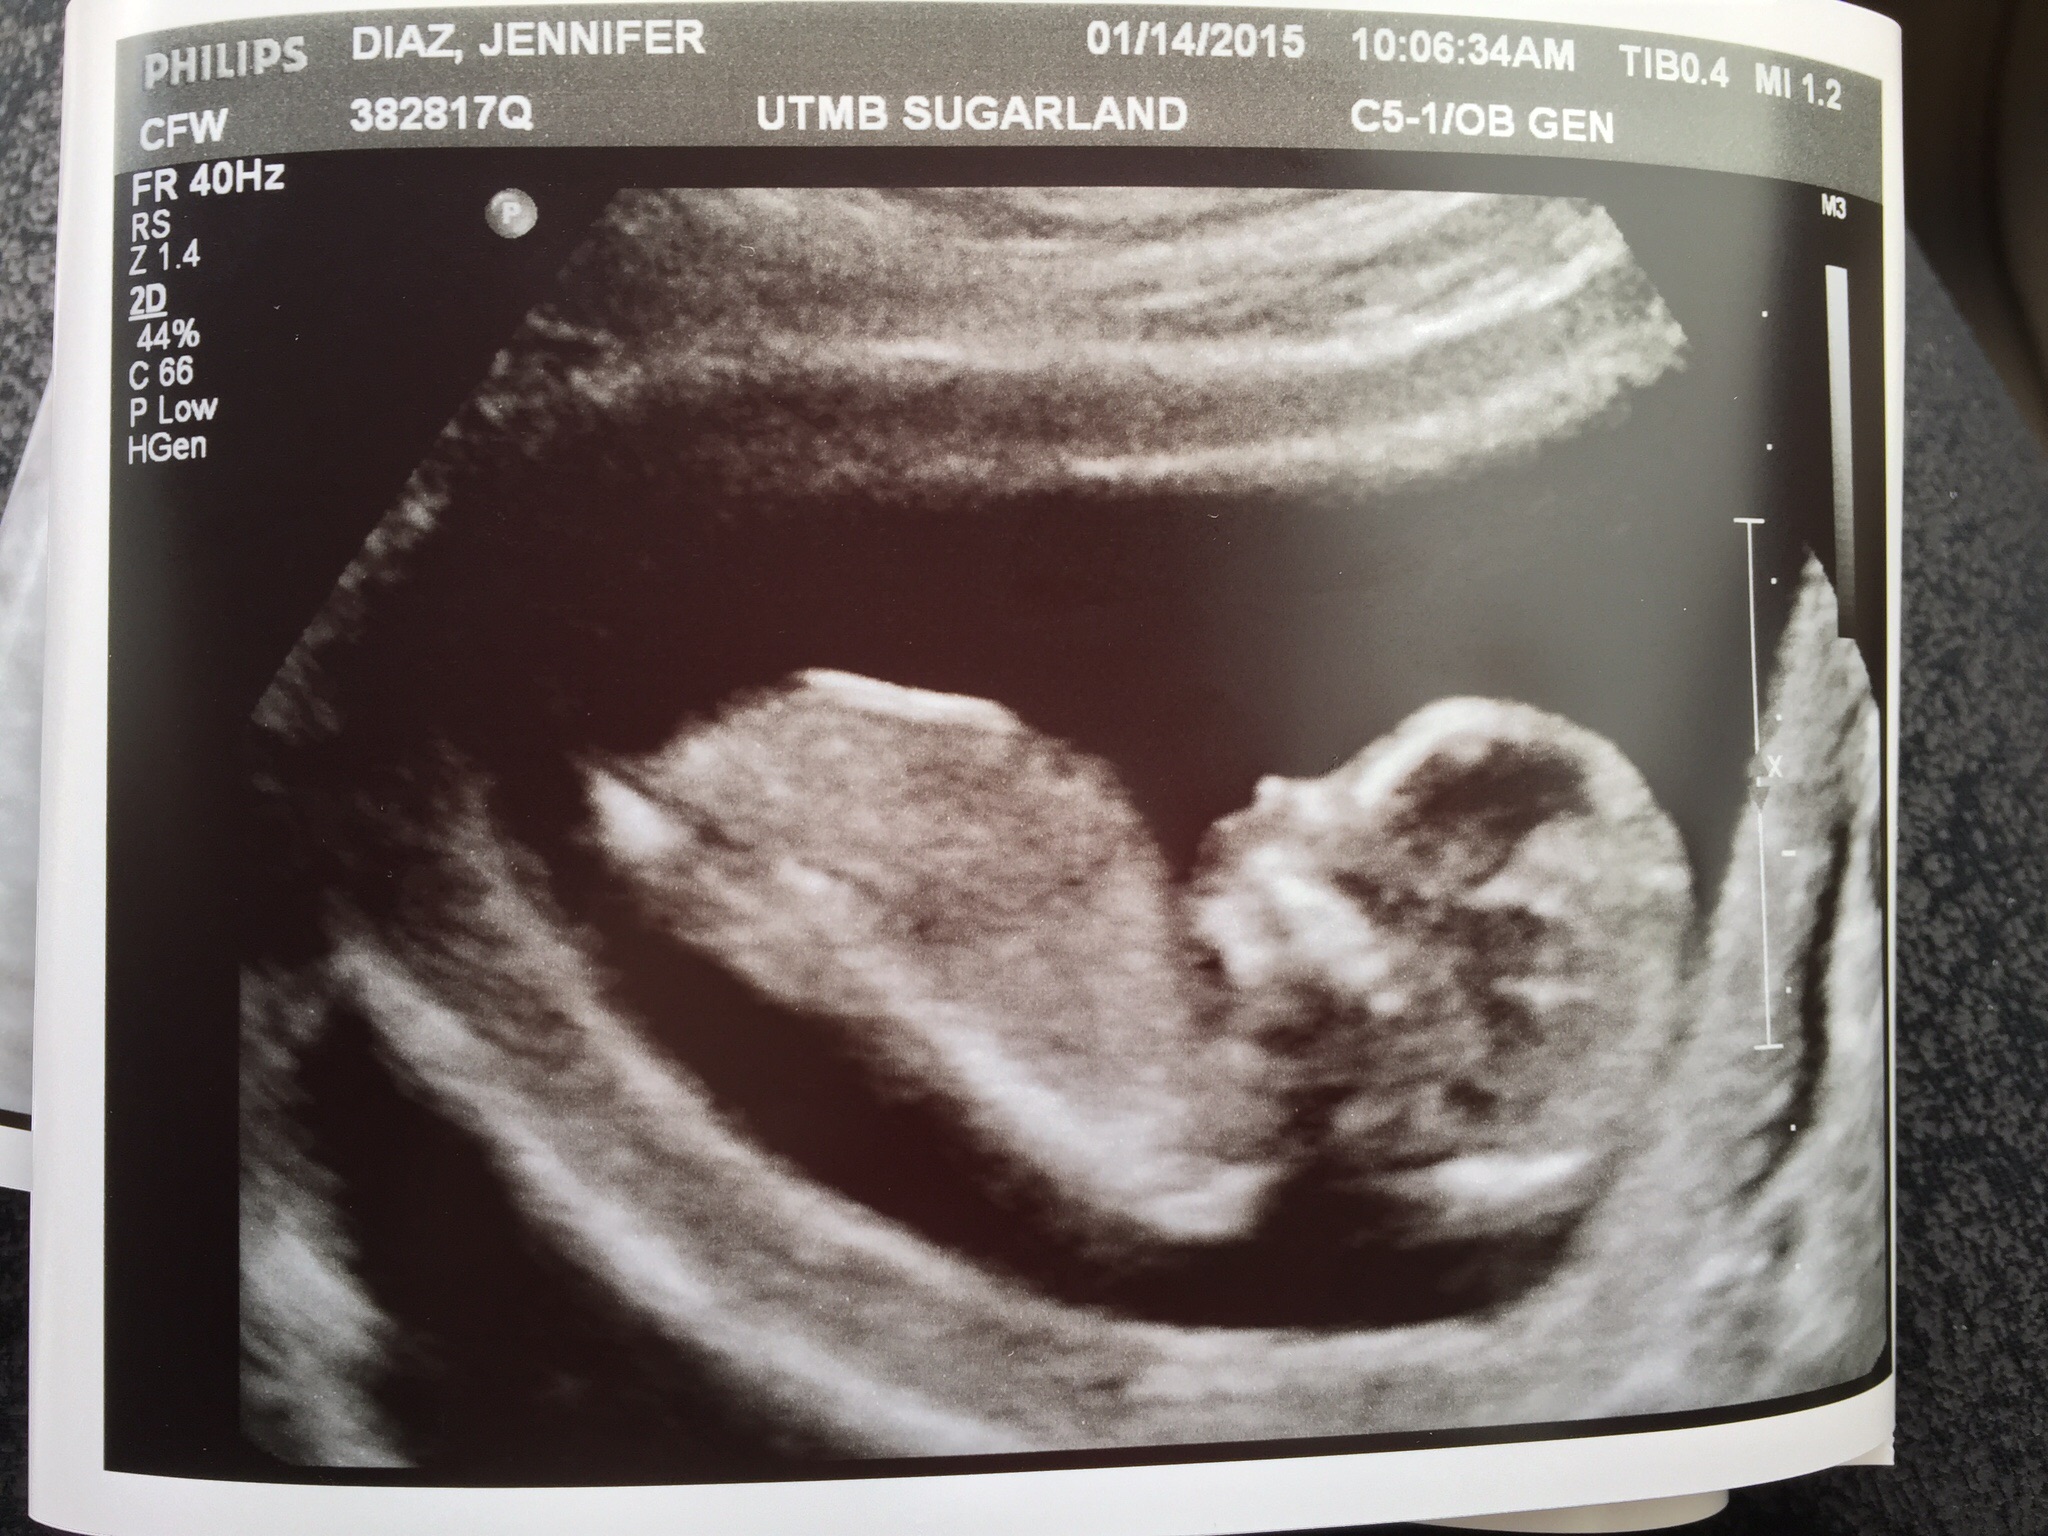

This just becomes more & more real to me. I'm so excited. 14 weeks & 4 days

& they gave me a gender prediction but I won't be sharing or confirming with anyone until the 18-20 weeks ultrasound.